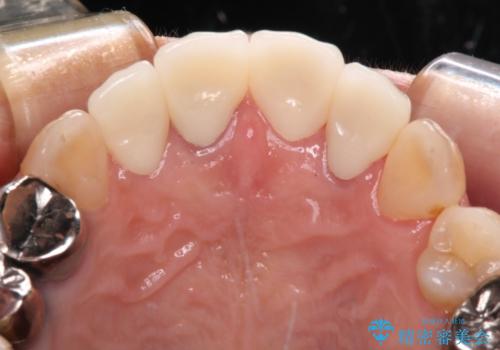

奥歯の治療をしている間に前歯の治療をどのように勧めるのか検討していただき、最終的には4歯を一度に治療し、審美的に仕上げることとしました。